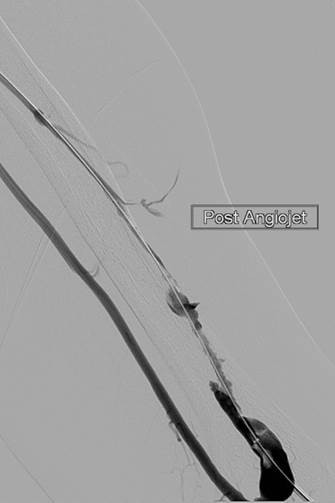

Thrombectomy of left brachial artery-axillary vein graft

Imaging post-AngioJet System activation in venous side of AV graft.

Imaging post-AngioJet System activation in arterial side of AV graft.